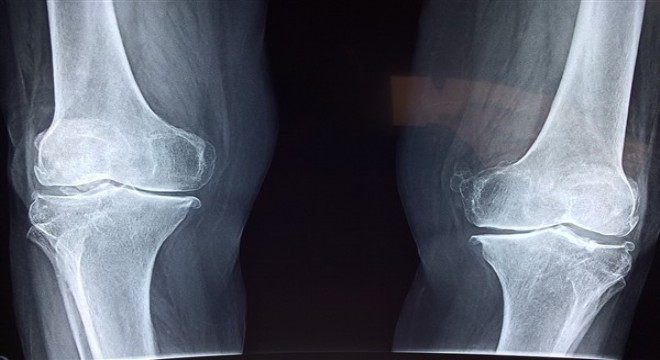

Eklem ağrıları kök hücre tedavisi ile son bulabiliyor

Diz, omuz veya kalçada yaşanan kıkırdak hasarları şiddetli eklem ağrılarına yol açabiliyor.

Diz, omuz veya kalçada yaşanan kıkırdak hasarları şiddetli eklem ağrılarına yol açabiliyor. Son yıllarda öne çıkan kök hücre tedavisi ise genellikle cerrahi yöntemler için uygun olmayan hastalarda başarılı sonuçlar vererek ağrıları ortadan kaldırıyor ve yaşam kalitesini yükseltiyor. Memorial Ataşehir Hastanesi Ortopedi ve Travmatoloji Bölümü’nden Prof. Dr. Haldun Orhun, kıkırdak hasarlarında uygulanan kök hücre tedavisi hakkında bilgi verdi.

Kök hücre tedavisi; cerrahi için henüz erken dönemde olan ya da ameliyat olmak istemeyen hastalarda, kıkırdak hasarının ilerlemesini durdurmak ve iyileşmesine destek olmak amacıyla kullanılmaktadır. Kıkırdak yaralanmasına maruz kalmış diz, kalça ve omuz gibi eklemlerde kök hücre kullanılmaktadır.Kullanım alanı açısından önemli özellikleri olan bu uygulamada, yaş, cinsiyet gibi faktörler ve hastalığın düzeyi çok önemlidir. Kök hücre, eklem kıkırdak kapasitesinin tamamına yakın kayıplarında uygulanabilecek bir işlem değildir. Uygun hasta seçimi çok önemlidir.